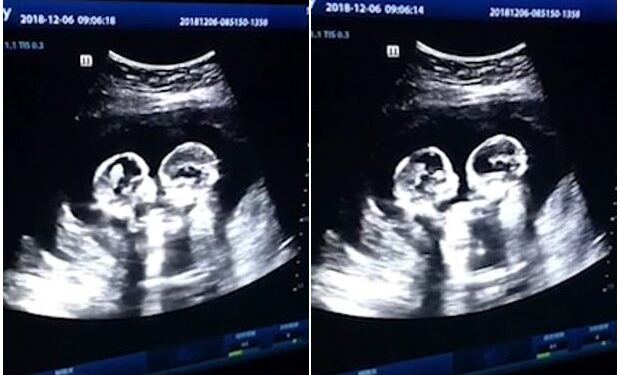

Μια έγκυος πήγε για το υπερηχογράφημα και όταν κοίταξε την οθόνη η καρδιά της “σταμάτησε”. Κανείς δεν μπορούσε να πιστέψει στα μάτια του. Η 24χρονη μοιράστηκε τη στιγμή στο Facebook και από τότε έχει γίνει viral. Τι ήταν αυτό που άφησε τους πάντες άφωνους;

Η χαριτωμένη στιγμή που τα δίδυμα στην οθόνη πιάστηκαν να ανταλλάσσουν ένα φιλί. Στα 12 χρόνια καριέρας τους, οι γιατροί δεν είχαν ξαναδεί παρόμοιο υπερηχογράφημα. “Ήταν τόσο συναρπαστικό που τα είδαμε έτσι. Δεν φανταζόμουν ότι θα ήταν τόσο κοντά μαζί, αλλά ήταν και ήταν τόσο όμορφο αυτό που είδαμε”.

Στην αρχή, ένα μωρό φιλούσε το άλλο μωρό στο μάγουλο. Στη συνέχεια ήρθαν πιο κοντά και έδωσαν ένα γρήγορο φιλί στα χείλη. Η 24χρονη είπε ότι ήταν “τόσο χαριτωμένο”.

Είναι φανερό ότι αυτά τα μικροσκοπικά κορίτσια θα γίνουν οι καλύτερες φίλες στη ζωή και οι γονείς τους έχουν αποδείξεις γι’ αυτό!